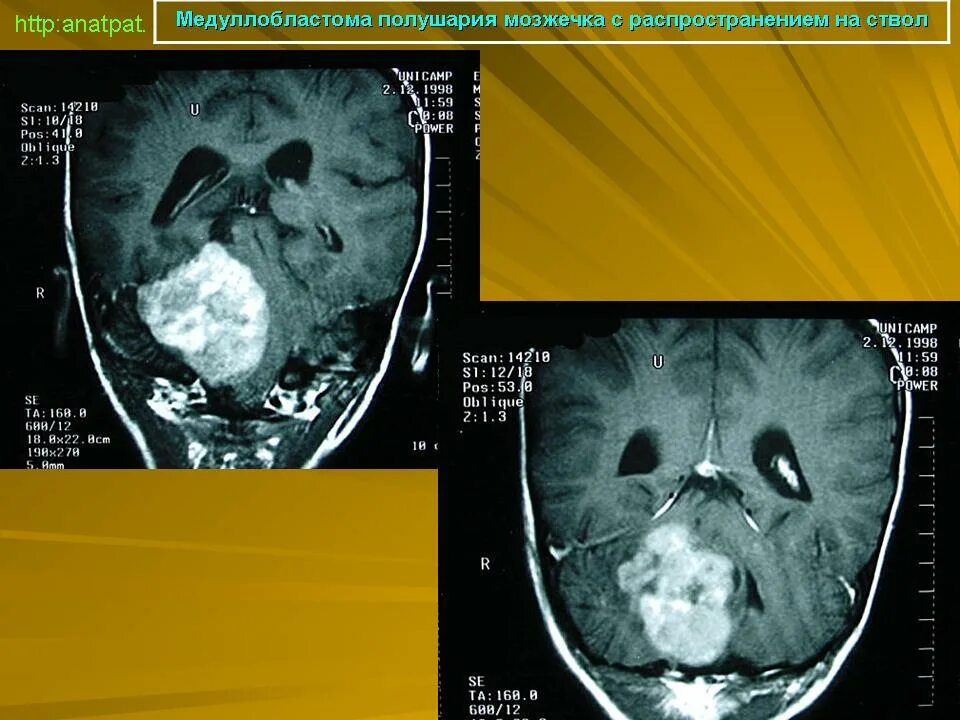

Медуллобластома это